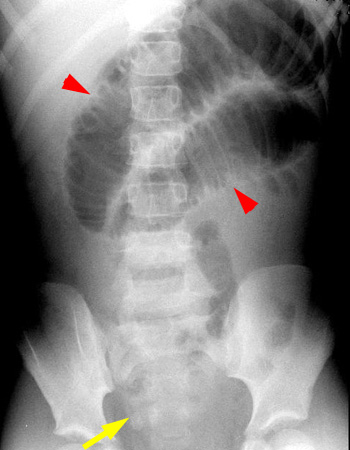

Plain film XR demonstrates a small bowel obstruction with an appendicolith faintly visualized in the RLQ.